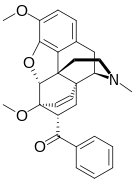

Oripavine derivatives

Thienorphine

- 7-PET

- Acetorphine

- Alletorphine (N-allyl-noretorphine)

- BU-48

- Buprenorphine

- Buprenorphine-3-glucuronide

- Cyprenorphine

- Dihydroetorphine

- Etorphine

- Homprenorphine

- 18,19-Dehydrobuprenorphine (HS-599)

- N-cyclopropylmethylnoretorphine

- Nepenthone

- Norbuprenorphine

- Norbuprenorphine-3-glucuronide

- Thevinone

- Thienorphine

Structures

| Oripavine derivatives | ||||

7-PET 7-PET |

Acetorphine Acetorphine |

Alletorphine Alletorphine |

BU-48 BU-48 |

Buprenorphine Buprenorphine |

Cyprenorphine Cyprenorphine |

Dihydroetorphine Dihydroetorphine |

Etorphine Etorphine |

Homprenorphine Homprenorphine |

18,19-Dehydrobuprenorphine 18,19-Dehydrobuprenorphine |

N-cyclopropylmethylnoretorphine N-cyclopropylmethylnoretorphine |

Nepenthone Nepenthone |

Norbuprenorphine Norbuprenorphine |

Thevinone Thevinone |

Thienorphine Thienorphine |